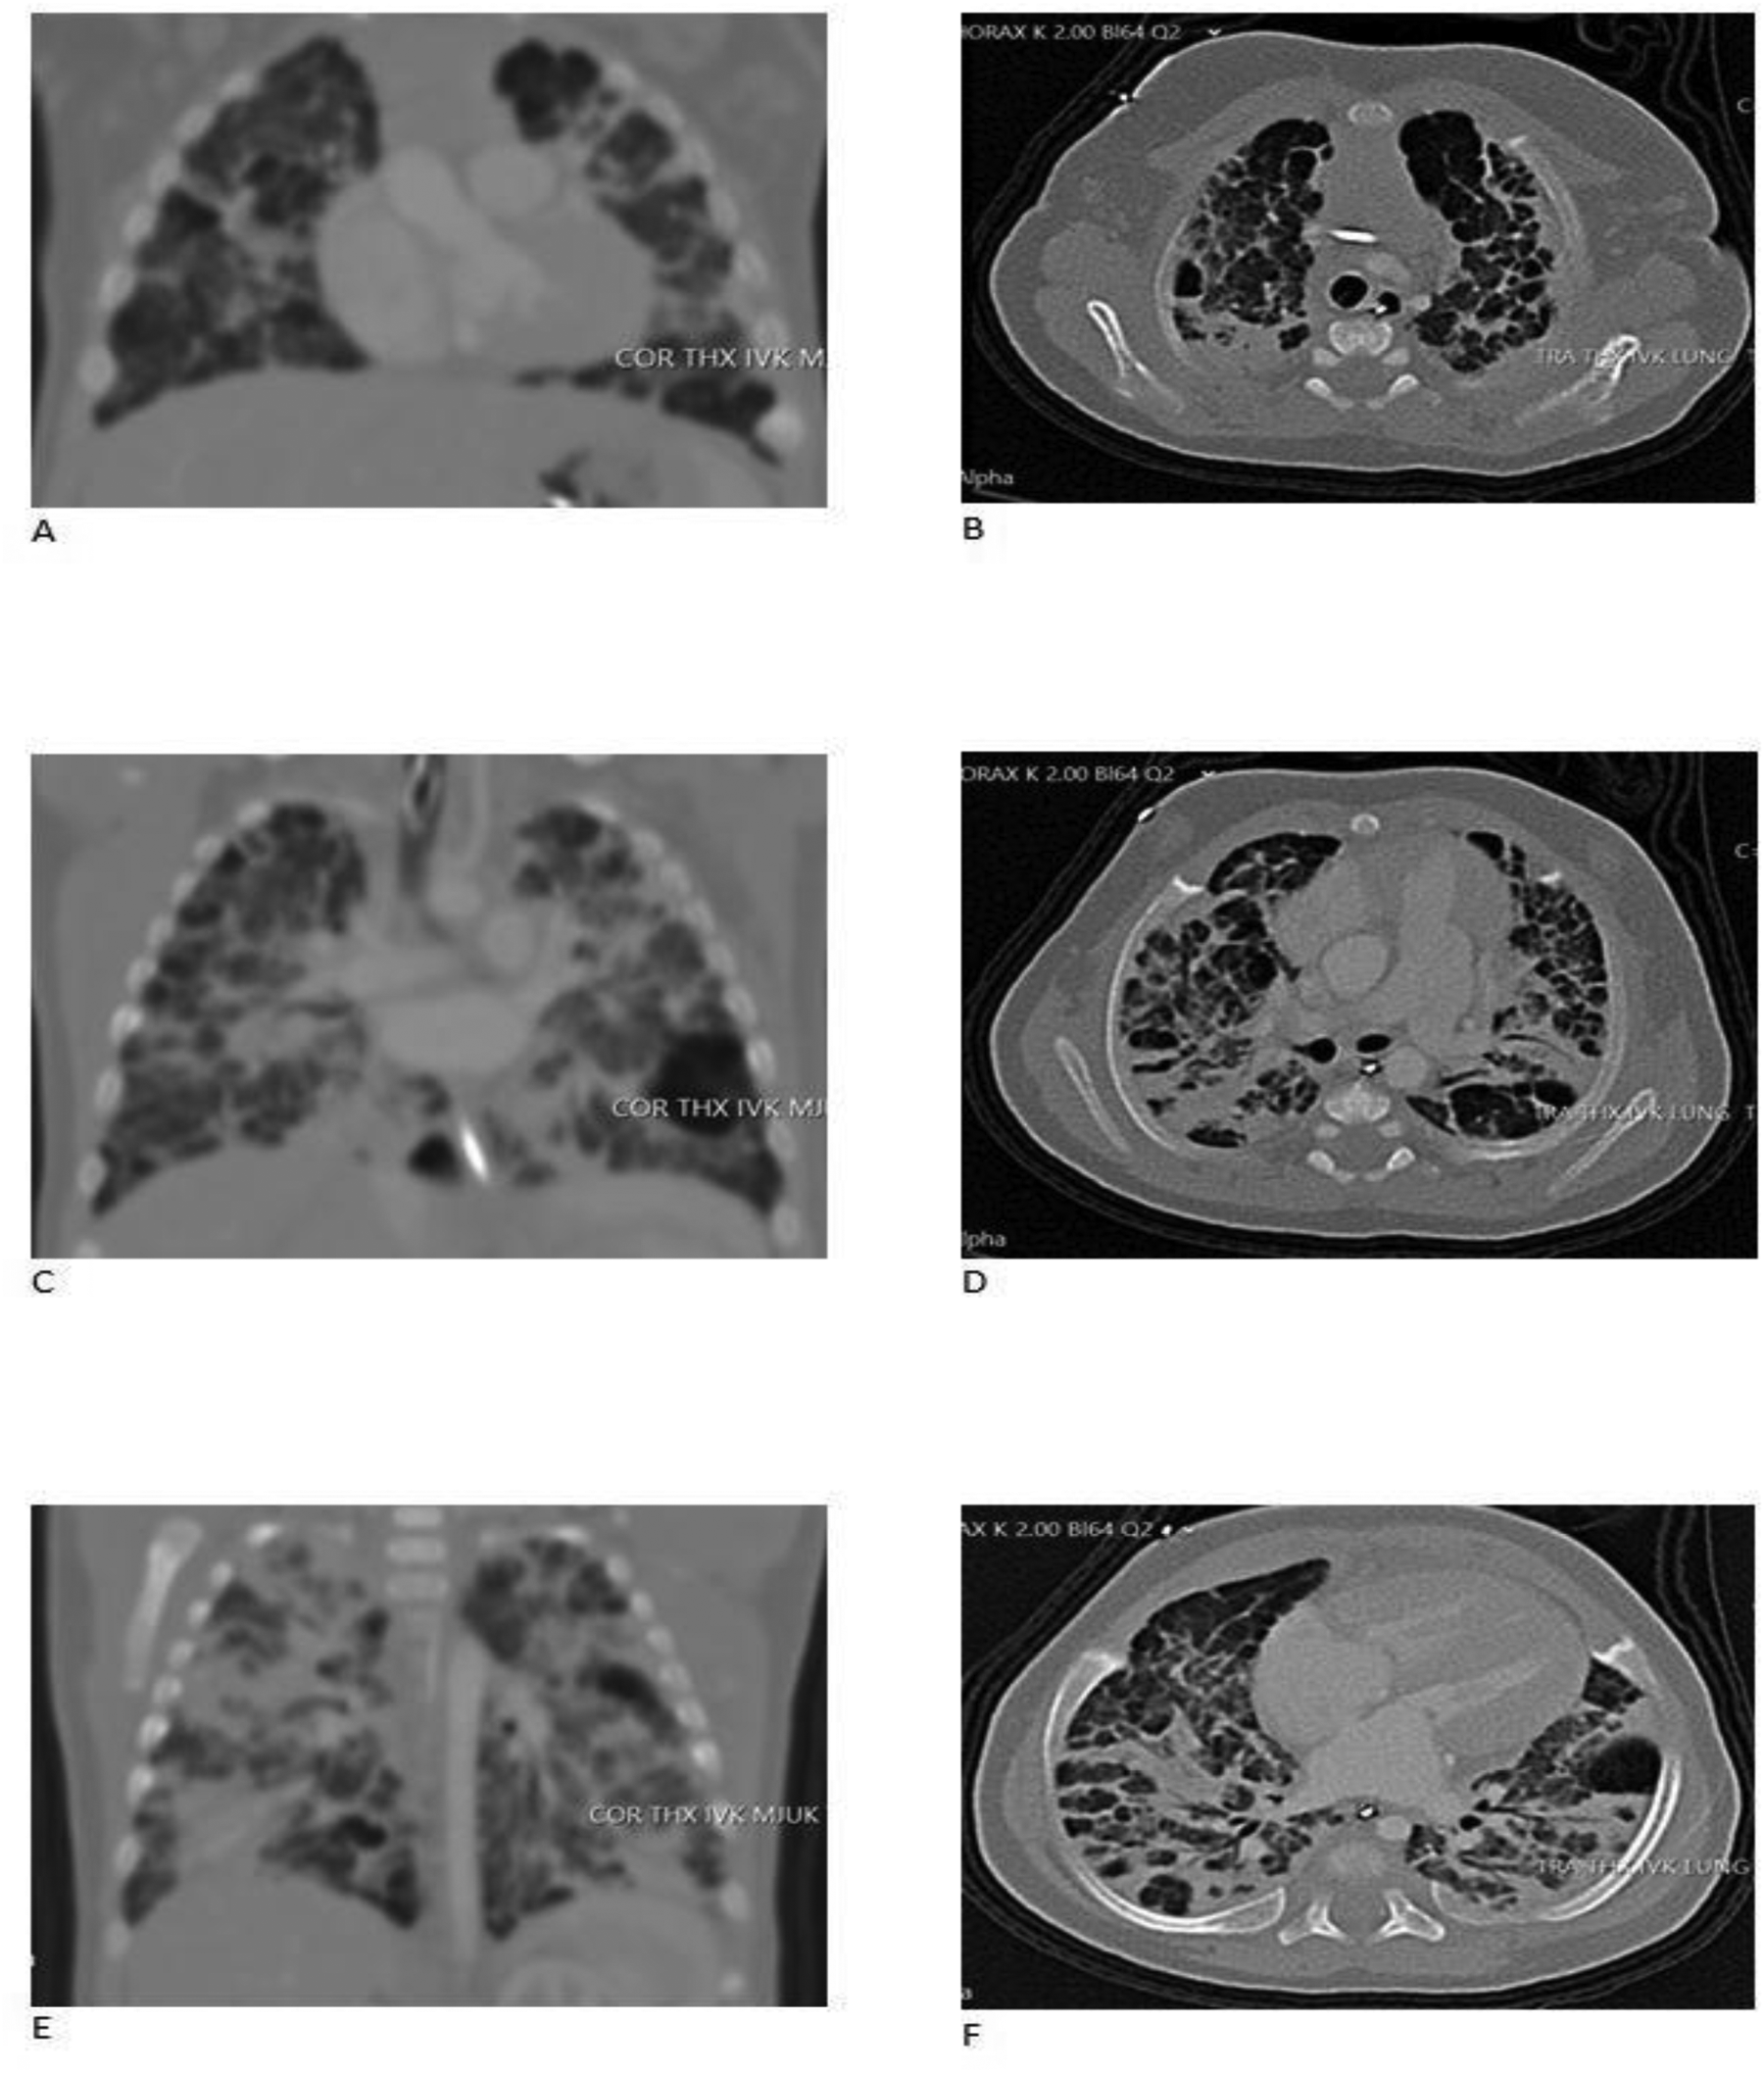

Figure 2

Ct scans with contrast of the chest. (A) CT (computed tomography) scan was performed at PMA (post-menstrual age) 41w before closure of the shunts. Frontal view on left, anterior to dorsal (A,C,E) and transverse view on right, apical to basal (B,D,F). Pulmonary venous obstruction was excluded and the PDA and ASD could be verified. Pronounced bilateral lung parenchymal abnormalities with crazy paving, ground glass, intralobular lines, thickening of interlobular septa, and dorsal consolidation were noticed in keeping with BPD. Consolidation of the middle lobe with no suspicion of intralobular sequestration was seen. Ventrobasal in the left lower lobe an 18 × 20 × 16 mm air filled cystic structure, probable a pneumatocele was diagnosed. Several small cystic changes were seen bilateral, especially in basal parts of the lung. A mild pulmonary edema could not be excluded.

The first cardiac ultrasound was performed at 6 days of age and revealed an atrial septal defect (ASD) and a patent ductus arteriosus (PDA, Vmax 1,8 m/s), both with significant left-to-right shunting. A reversible ante-to-retrograde blood flow was noticed in mesenteric blood vessels, which indicated a significant run-off phenomenon of blood flow from the gut into the lung with diastolic left-to-right shunt in the PDA, but no NEC developed. Ibuprofen (PEDEA®) was administered intravenously with five doses with no effect on the PDA. The right ventricle was dilated due to pulmonary overcirculation and on some cardiac ultrasounds judge to be slightly hypertrophied. Left ventricle had normal systolic contractility. A CT scan ( Figure 2 ) and cardiac ultrasounds clearly showed that all four pulmonary veins enter the left atrium without obstruction. The ASD was not suitable for device closure due to its size and location. A cardiac catheterization was discussed, but the cardiologists refrain from it, since pulmonary vein stenosis had been excluded, device closure was not needed and the PH was regarded to be caused by the left-to-right shunts. A surgical closure of the ASD and PDA was advocated and successfully done at 4 months of age.